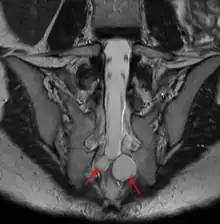

MRI

MRI sagittal image of sacral and dorso-lumbar perineural cysts.

MRI, or Magnetic Resonance Imaging, is considered the imaging study of choice in identifying Tarlov cysts. MRI provides better resolution of tissue density, absence of bone interference, multiplanar capabilities, and is noninvasive. Plain films may show bony erosion of the spinal canal or of the sacral foramina. On MRI pictures, the signal is the same as the CSF one.

If MRI made with a contrast medium:

• The signal in the cyst is the same as in the dural bag.

• The signal for cysts due to traumas is a little stronger at the periphery or nerve root location.

• The signal is more important for other causes: synovial cysts, dermoïdes or épidermoïdes cysts, teratomes.[7][25][26]